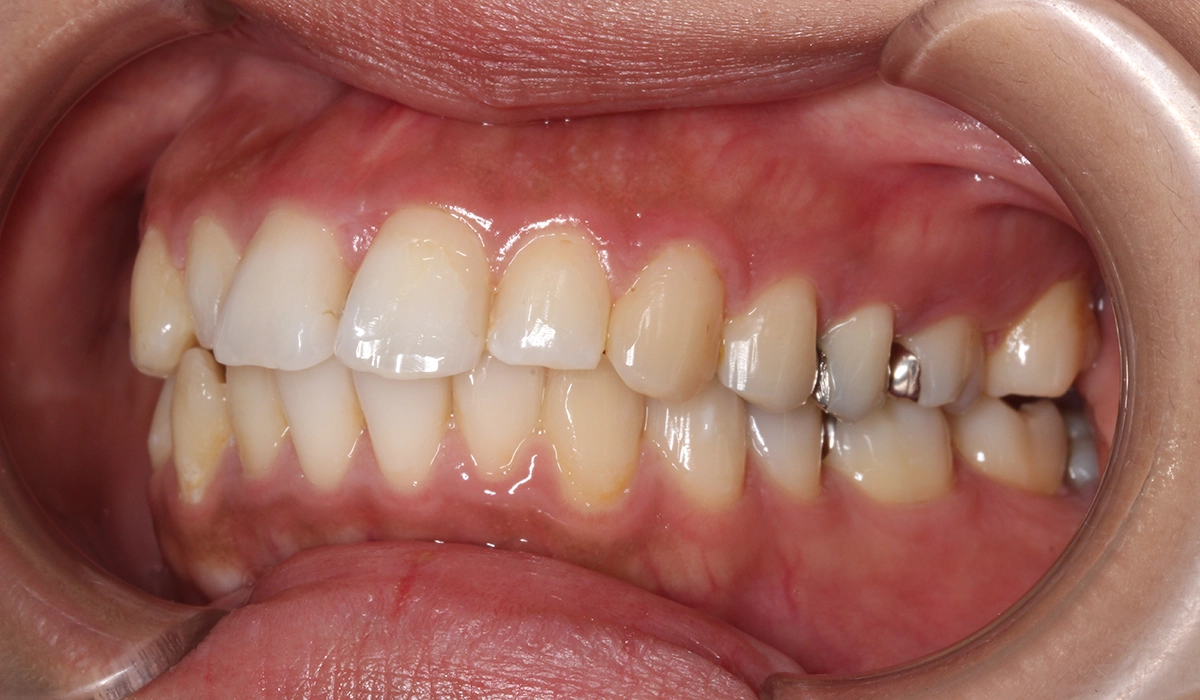

術前:右側

術後:右側

今回ご紹介する患者様は、上下の歯並びのガタツキを気にされており、矯正検査後叢生Ⅱ級と診断いたしました。

| 治療内容 | 上下の歯並びのガタツキを気にされており、矯正検査後叢生Ⅱ級と診断いたしました。 |